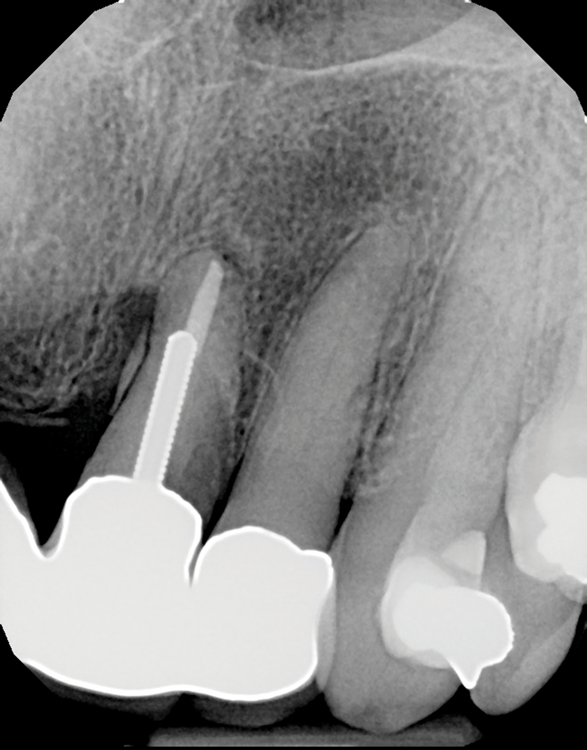

(7.) Try-in, seat/buildup, and completed views of prefabricated post-sleeve system.

Figure 7

Adjustable Post-Sleeve

An adjustable post and sleeve system has been recently introduced comprised of a single-size post and a tapered sleeve of the same material. The sleeve can be utilized, when necessary, to customize the post in cases involving flared or overprepared canals. After the post is inserted, the sleeve slides down onto it and into the flared canal to whatever depth is required for the best fit (Figure 7). The sleeve significantly reduces the volume of cement required to fill the coronal area of the pulp chamber and is much stronger than many resins that have been previously used for this purpose.